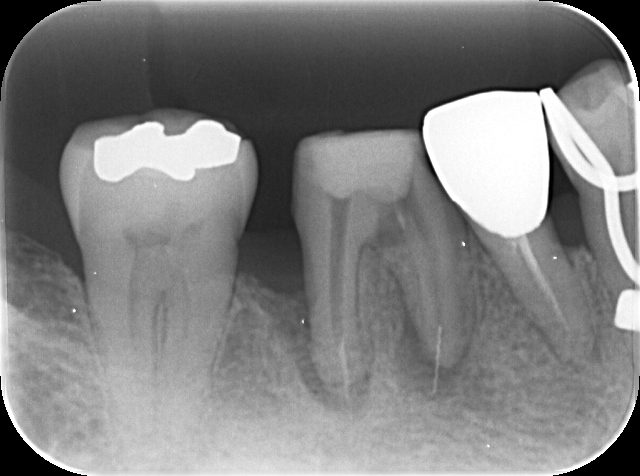

下のレントゲン写真は、下顎第一大臼歯の近心根(写真では右側の歯根)に、根管治療で使用するファイルが破折し、一部は歯根の先端から飛び出ている状態が認められます。

このような場所で破折しているとルーペで確認することは非常に困難であり、マイクロスコープで対応するしかありません。